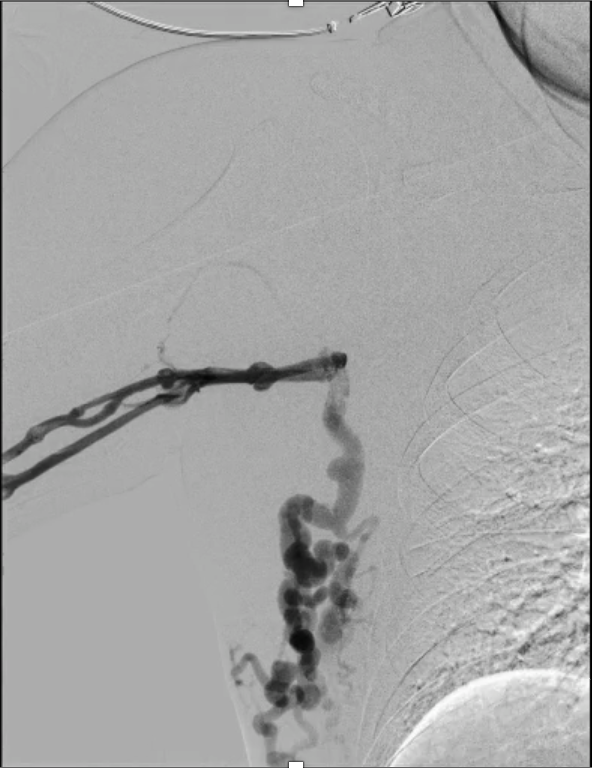

Real-time echo-guided puncture of both basilic veins was performed, and 6 Fr sheaths were inserted bilaterally. Bilateral venography demonstrated complete occlusion of both innominate veins with extensive collateral formation. A V-18 wire was advanced through the left brachiocephalic vein lesion, followed by a Sterling 5.0 ¡¿ 80 mm balloon inflated to 12 atm from the SVC to the left brachiocephalic vein for angioplasty. The wire was then exchanged for a Connect Flex 0.018¡È ¡¿ 300 cm wire to cross the right brachiocephalic vein lesion toward the internal thoracic connection (ITC). A Sterling 5.0 ¡¿ 80 mm balloon was inflated to 10 atm from the SVC to the right brachiocephalic and right axillary veins for angioplasty; however, the right axillary vein lesion failed to dilate adequately. A Mustang 10 ¡¿ 80 mm balloon was subsequently used and inflated to 20 atm, yet residual stenosis persisted. The wire was exchanged for a Roadrunner wire, and a Conquest 40 balloon was advanced and inflated to 30 atm for high-pressure angioplasty of the right innominate, axillary, and cephalic veins. Subsequently, Wallstent 16 ¡¿ 90 mm was deployed from the SVC to the left brachiocephalic vein, and Wallstent 14 ¡¿ 90 mm was deployed from the SVC to the right brachiocephalic vein. Final post-dilatation was performed using a Mustang 12 ¡¿ 80 mm balloon inflated to 10 atm for both brachiocephalic vein stents.

Successful endovascular revascularization was achieved in a patient with superior vena cava syndrome secondary to chronic bilateral brachiocephalic vein occlusion. High-pressure balloon angioplasty followed by bilateral stent deployment restored venous patency and relieved symptoms. This case highlights the feasibility and effectiveness of endovascular therapy in dialysis-related chronic central venous obstruction.